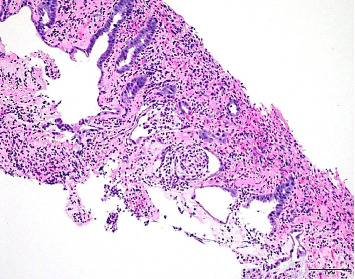

本病例报告描述了一例罕见的非甾体抗炎药(NSAID)诱导的局灶性结肠肉芽肿肿块,类似恶性结肠肿块。它强调了非甾体抗炎药相关胃肠道并发症的诊断挑战,并强调了在类似的表现中考虑这些原因的重要性。及时识别和停用非甾体抗炎药可以防止不必要的手术干预,并促进症状的缓解。本病例强调了详细用药史和谨慎使用非甾体抗炎药以减少不良胃肠道反应风险的价值。

This case report describes a rare occurrence of nonsteroidal anti-inflammatory drugs (NSAID)-induced focal colonic granulomatous mass mimicking a malignant colonic mass. It highlights the diagnostic challenges of NSAID-related gastrointestinal complications and stresses the importance of considering such causes in similar presentations. Prompt recognition and withdrawal of the offending NSAID can prevent unnecessary surgical intervention and facilitate symptom resolution. This case underscores the value of a detailed medication history and cautious NSAID use to reduce the risk of adverse gastrointestinal effects.